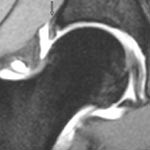

Degenerativ labrum viste økt signalintensitet i labrum uten affeksjon av overflaten med inntakt recess hos to pasienter (fig 3) og med manglende fremstilling av recess hos tre pasienter (fig 4). Sistnevnte ansees forårsaket av labrumhypertrofi. Labrumruptur ble diagnosisert hos ti pasienter. Ruptur ble beskrevet når man kunne identifisere kontrast mellom labrum og acetabulum (fig 5) eller imbibering av kontrast i labrum (fig 6). Alle rupturene satt i øvre del av labrum.To av disse pasientene er operert, og vårt funn ble verifisert. Begge var aktive fotballspillere, og de hadde henholdvis stadium 2B og stadium 3B ved MR-artrografi. Dette samsvarte med de artroskopiske funn. Den tredje pasienten som er operert, viste forandringer forenlig med villonodulær synovitt. Også dette ble verifisert ved artroskopi (fig 7).

Vi brukte Czerny og medarbeideres klassifikasjon av labrumskader ved MR-artrografi (2). Stadium 0 er normal labrum. Stadium 1 viser økt intralabral signalintensitet, forenlig med degenerativ labrum. Stadium 2 viser imbibering av kontrast inn i labrum, forenlig med ruptur. Stadium 3 viser kontrast mellom labrum og acetabularbrusken, forenlig med avrivning av labrum fra acetabulum. Ved bevart recess i stadium 1 – 3 brukes A i tillegg, mens det ved manglende fremstilling av sulcus brukes bokstaven B. Stadium B tilsier at labrum er hypertrofiert. I praksis betyr det at stadium 2 og stadium 3 viser patologiske forandringer i labrum som vil kunne behandles med ortopedisk intervensjon.